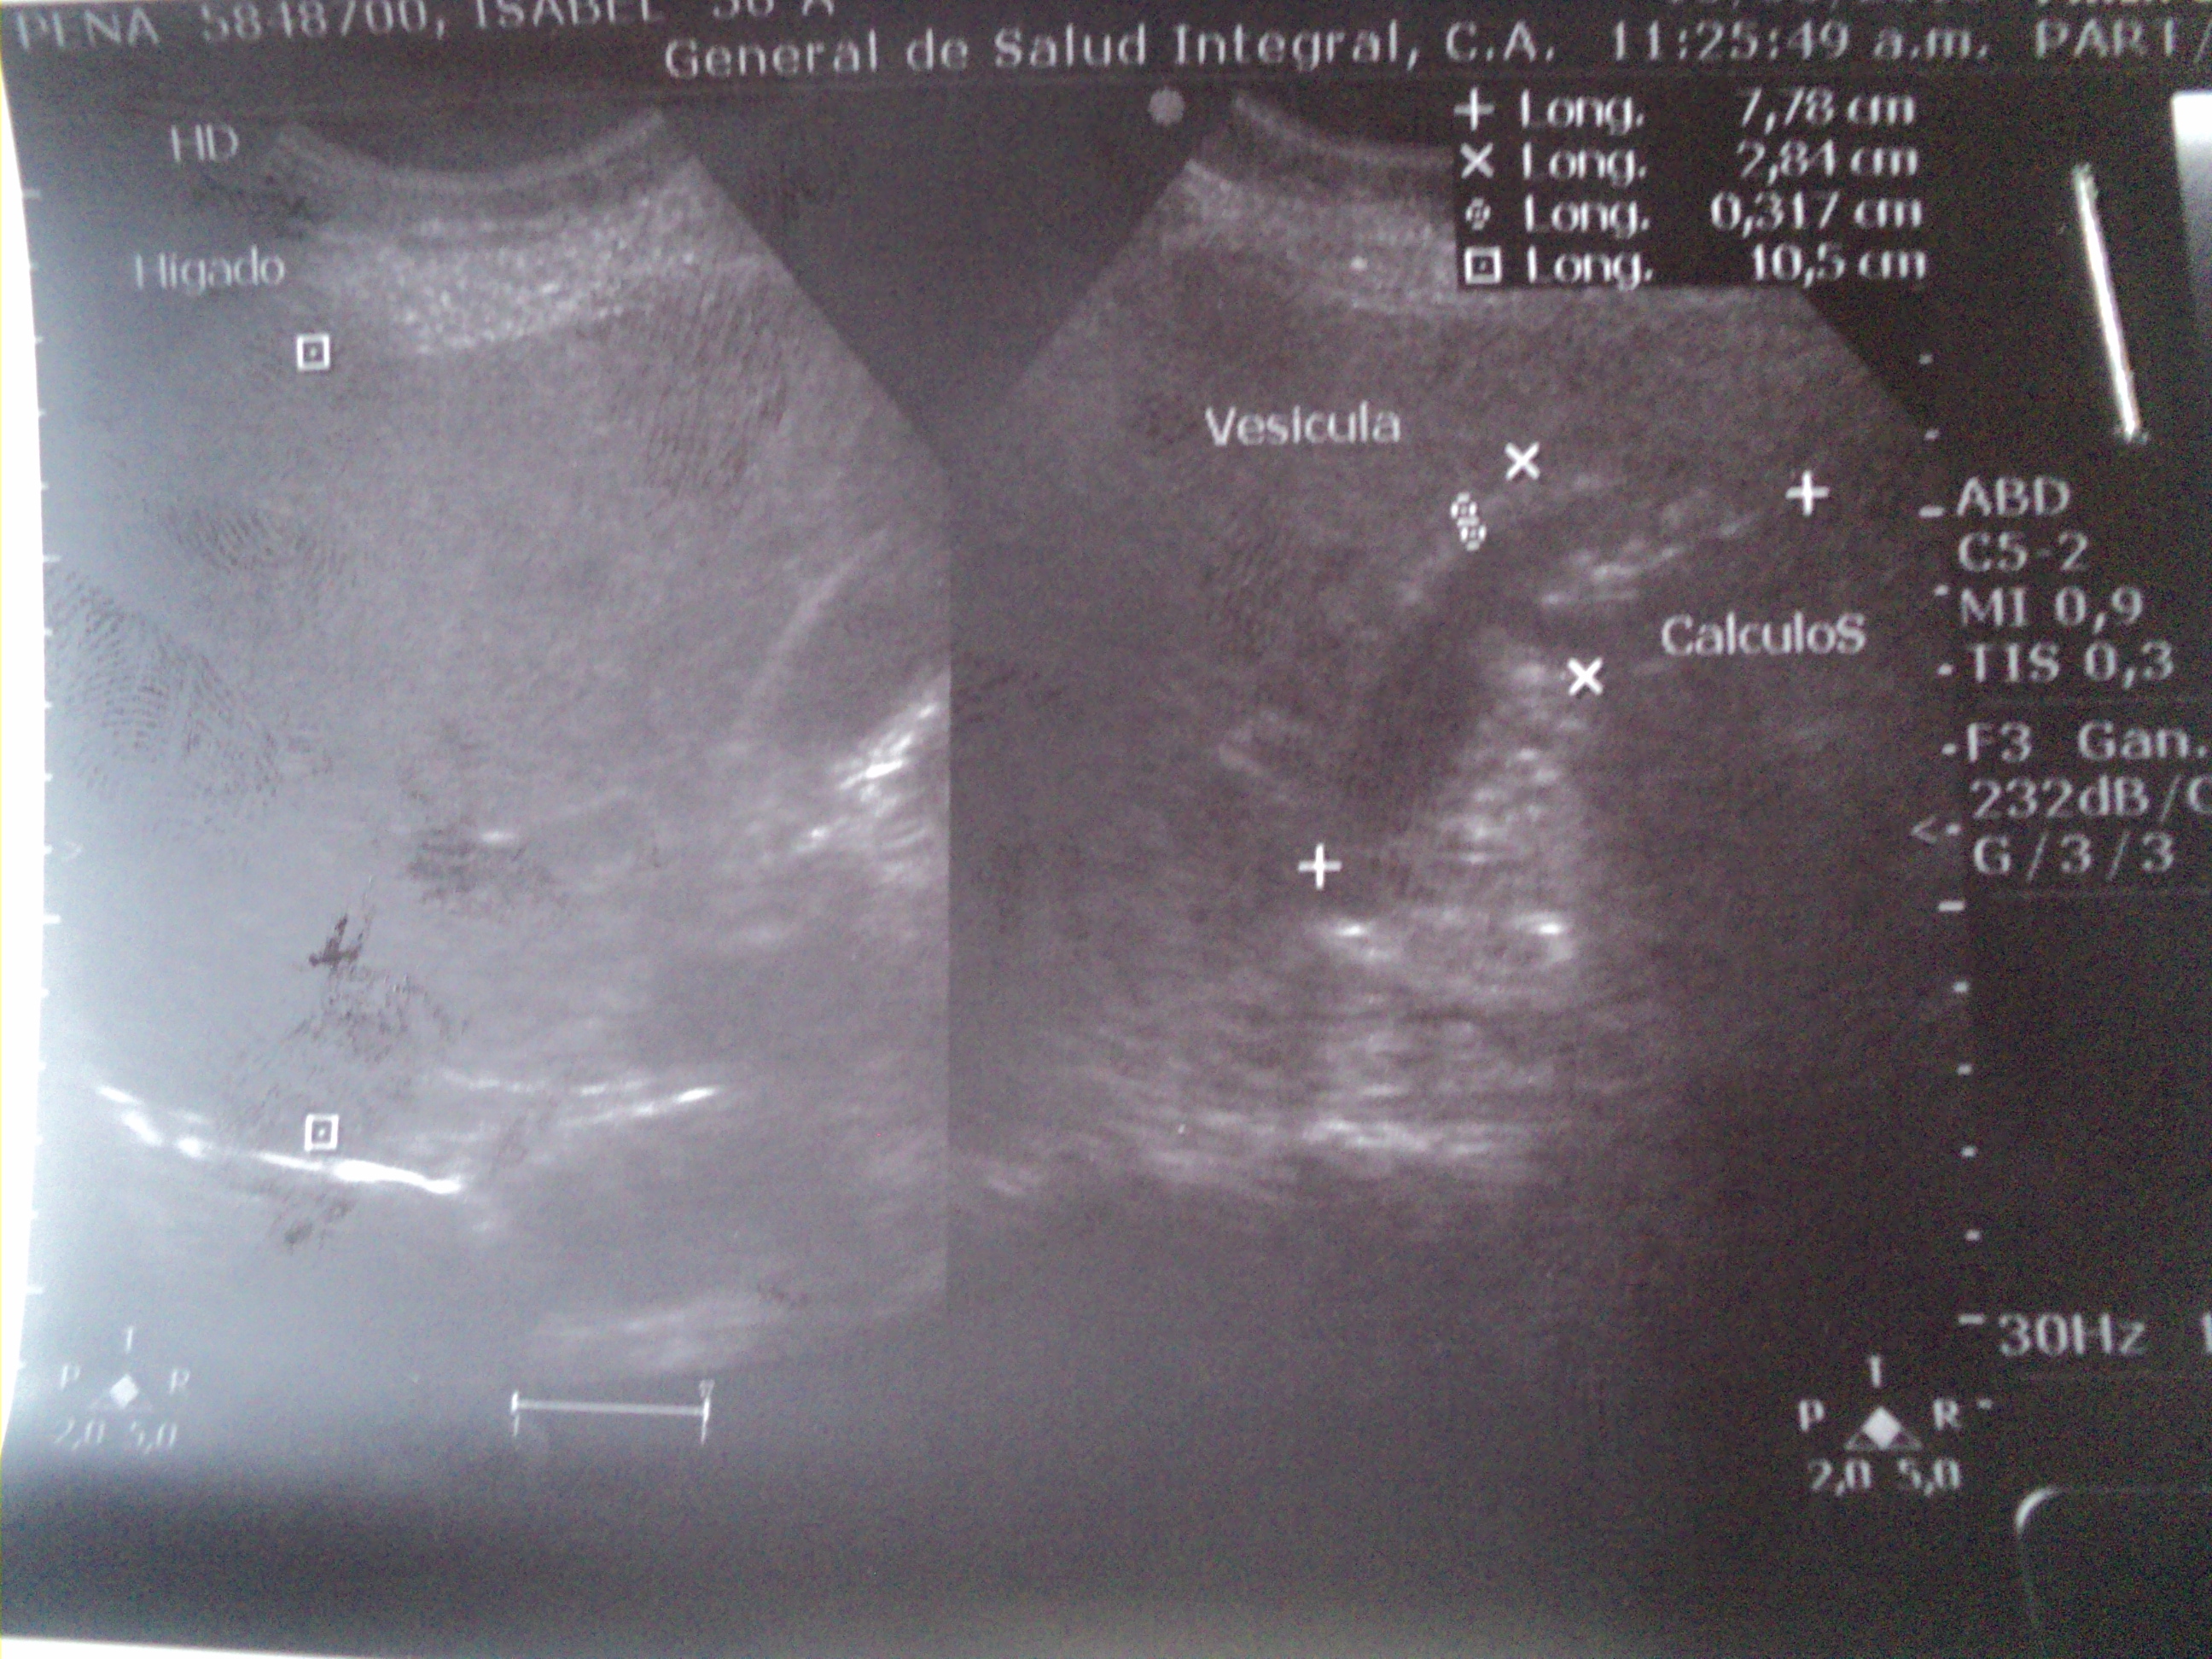

I want to tell you that today I went to do my second abdominal echogram to know how the calculations process continues and I was very happy but then the doctor told me that it was not good news.

When the doctor said the size of the stones I made the mental comparison with the last echogram. In the first, the size was 5.1 mm and now they were reduced to the highest in 2.5, for me it means improvement but for her it is a risk.

He told me that when a calculus reduces its size, it is more likely that it will try to go out and obstruct the vesicle duct that is of small size.